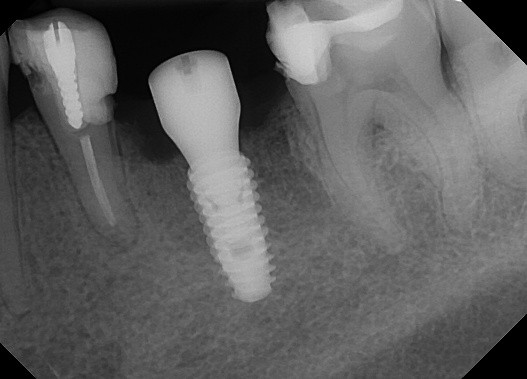

Which of the following is true regarding dental implant at site 2.6?

Which of the following is true regarding dental implant at site 3.6?

Regarding dental implant at site 3.6, there is evidence of